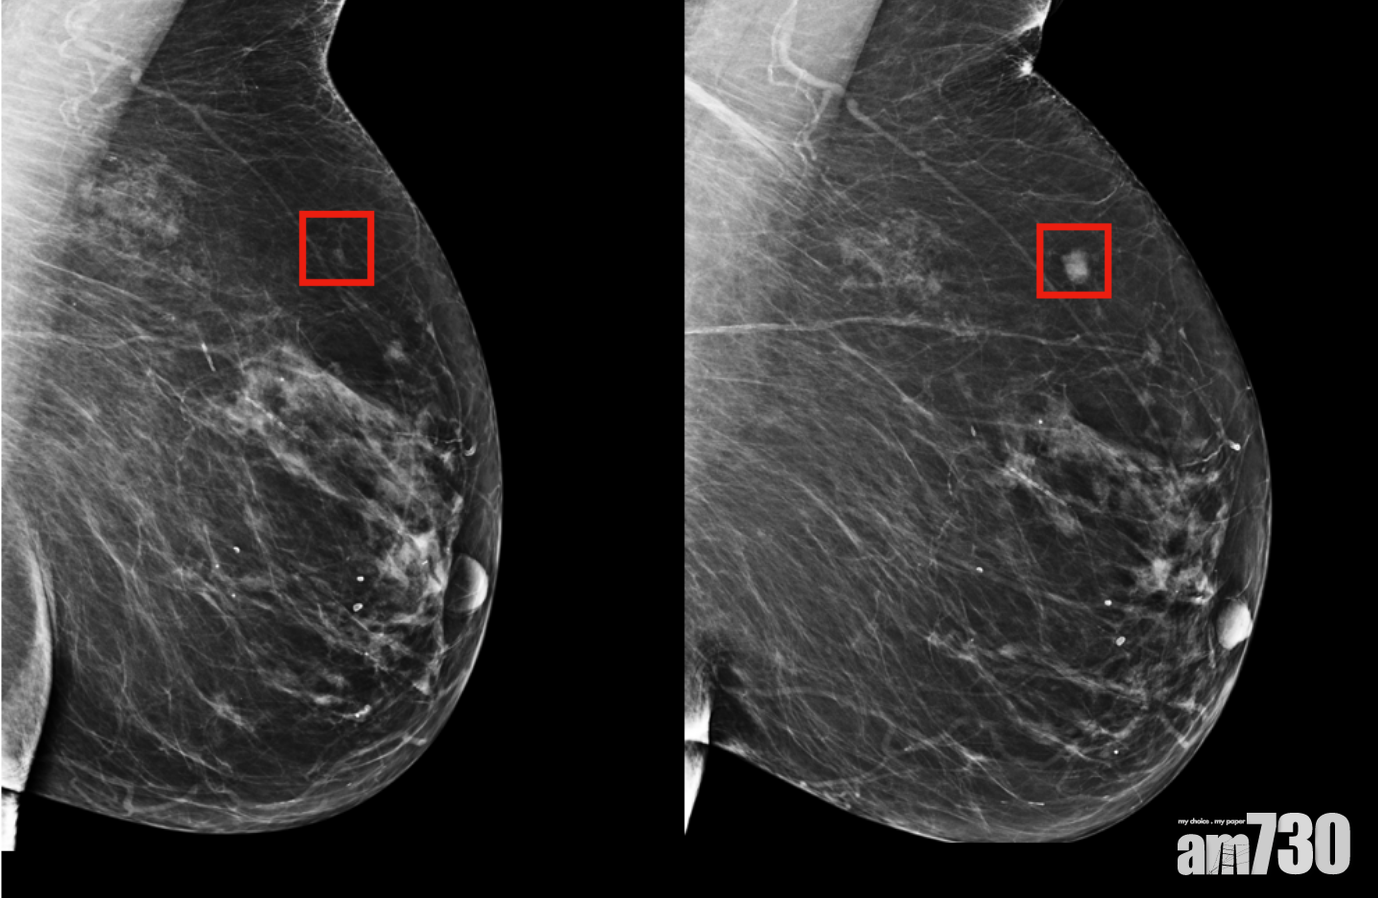

美國麻省理工學院率領的科研團隊,設計了一款AI風險檢測工具,能夠提早5年預測乳癌風險。(示意圖片)

系統通過學習多達90,000張乳房X光片,能夠辨識出乳房組織的任何一個微妙複雜變化。(MIT)

由美國麻省理工學院的「MIT計算機科學與人工智能實驗室」,聯同馬薩諸塞州綜合醫院的團隊,創建了一種新深度學習AI模型,比起傳統醫生從檢查人士的X光片識別出有可能患乳癌的費時做法,系統通過學習多達90,000張乳房X光片,能夠細緻地辨識出乳房組織的任何一個微妙複雜變化,藉此演算出未來5年患乳癌的機率。團隊稱新系統檢測出最高風險的可靠有31%,相比其他模型的18%還要高。